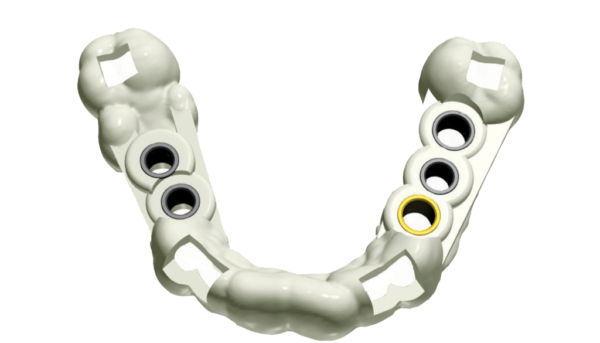

El 3D I-Max se puede ajustar para adaptarse a todas las cirugías